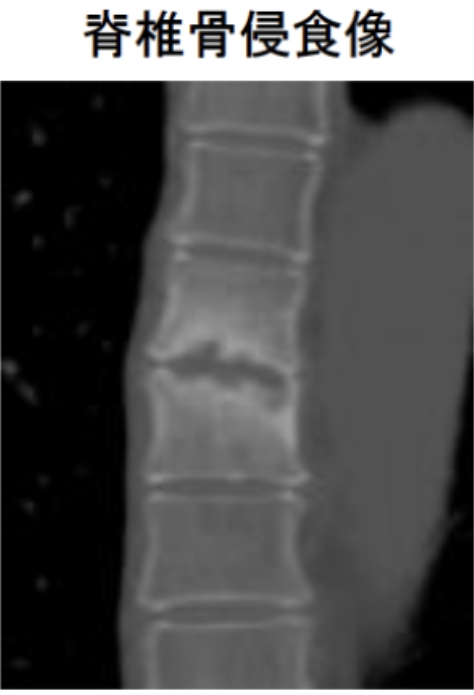

胸鎖関節を含め、関節炎に対してはエコー検査が診断に有用です。また脊椎や仙腸関節病変は、レントゲンやCTで骨病変、MRIで炎症の有無を確認することが出来ます。